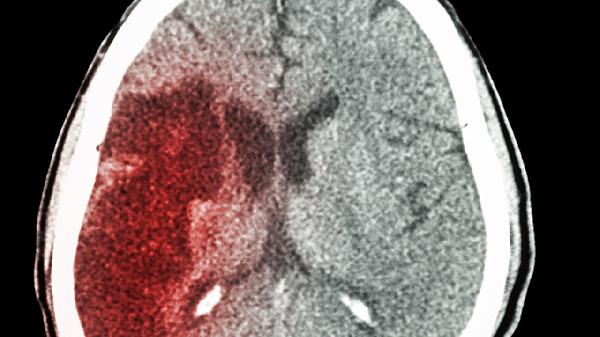

2、血栓风险降低

血液稀释后血小板不易聚集,就像早高峰加了车道。临床观察发现,这个习惯坚持三年以上的人,血管健康度有明显提升。